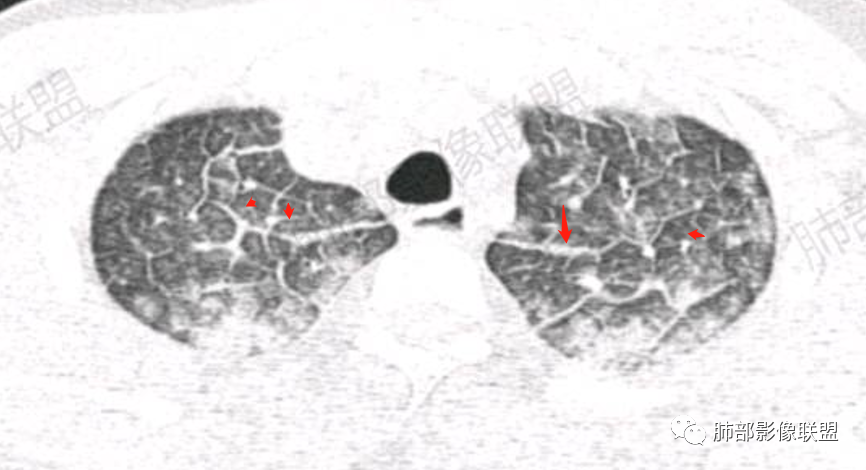

双肺上叶,下叶背段多发斑片状实变影,以胸膜下分布为主,部分重力作用,以背侧为主,部分小叶间质增厚,部分周围伴有散在磨玻璃影,边界欠清,临床急性病程,血象增及PCT明显增高,意识模糊,考虑:吸入性肺炎?鉴别:AHP?CEP?PCP

37岁男性 气促 两肺对称分布磨玻璃及小叶间隔增厚,两肺上叶后段及下叶背段为著,有重力分布,下部密度较高,请结合病史排查肺水肿,理化性肺泡损伤

影像:两肺上叶小叶间隔增厚,斑片,腺泡结节,重力分布,下肺不累及

对称性小叶间隔增厚

高密度影重力趋势

病灶的分布以上肺为主

确实要考虑吸入,倾向于吸入的是气体类的可能,因为朝上走

结合病史,最终诊断是 “急性烟雾吸入性肺损伤”,影像学表现主要是肺水肿及弥漫性肺泡损伤改变,因为烟雾气体吸入肺内分布以上肺显著,因此影像学表现也是累及上肺更明显。损伤因素包括大量一氧化碳 二氧化碳 一氧化氮等燃烧产生的有毒气体,也有烟雾粉尘颗粒对气道黏膜的损伤。